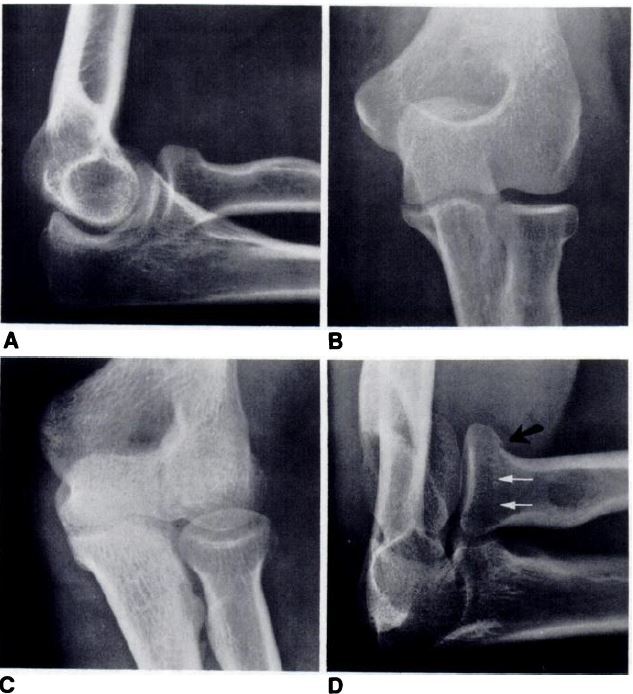

1. 촬영 목적 : elbow 4 view 후에도 잘 보여지지 않는 capitellum, radial head + neck 등을 보며, 윤활액이 많이 포함 된

Humeroradial Joint을 관찰

그림) 기본 영상검사에도 안보이는 병변이 관찰됨